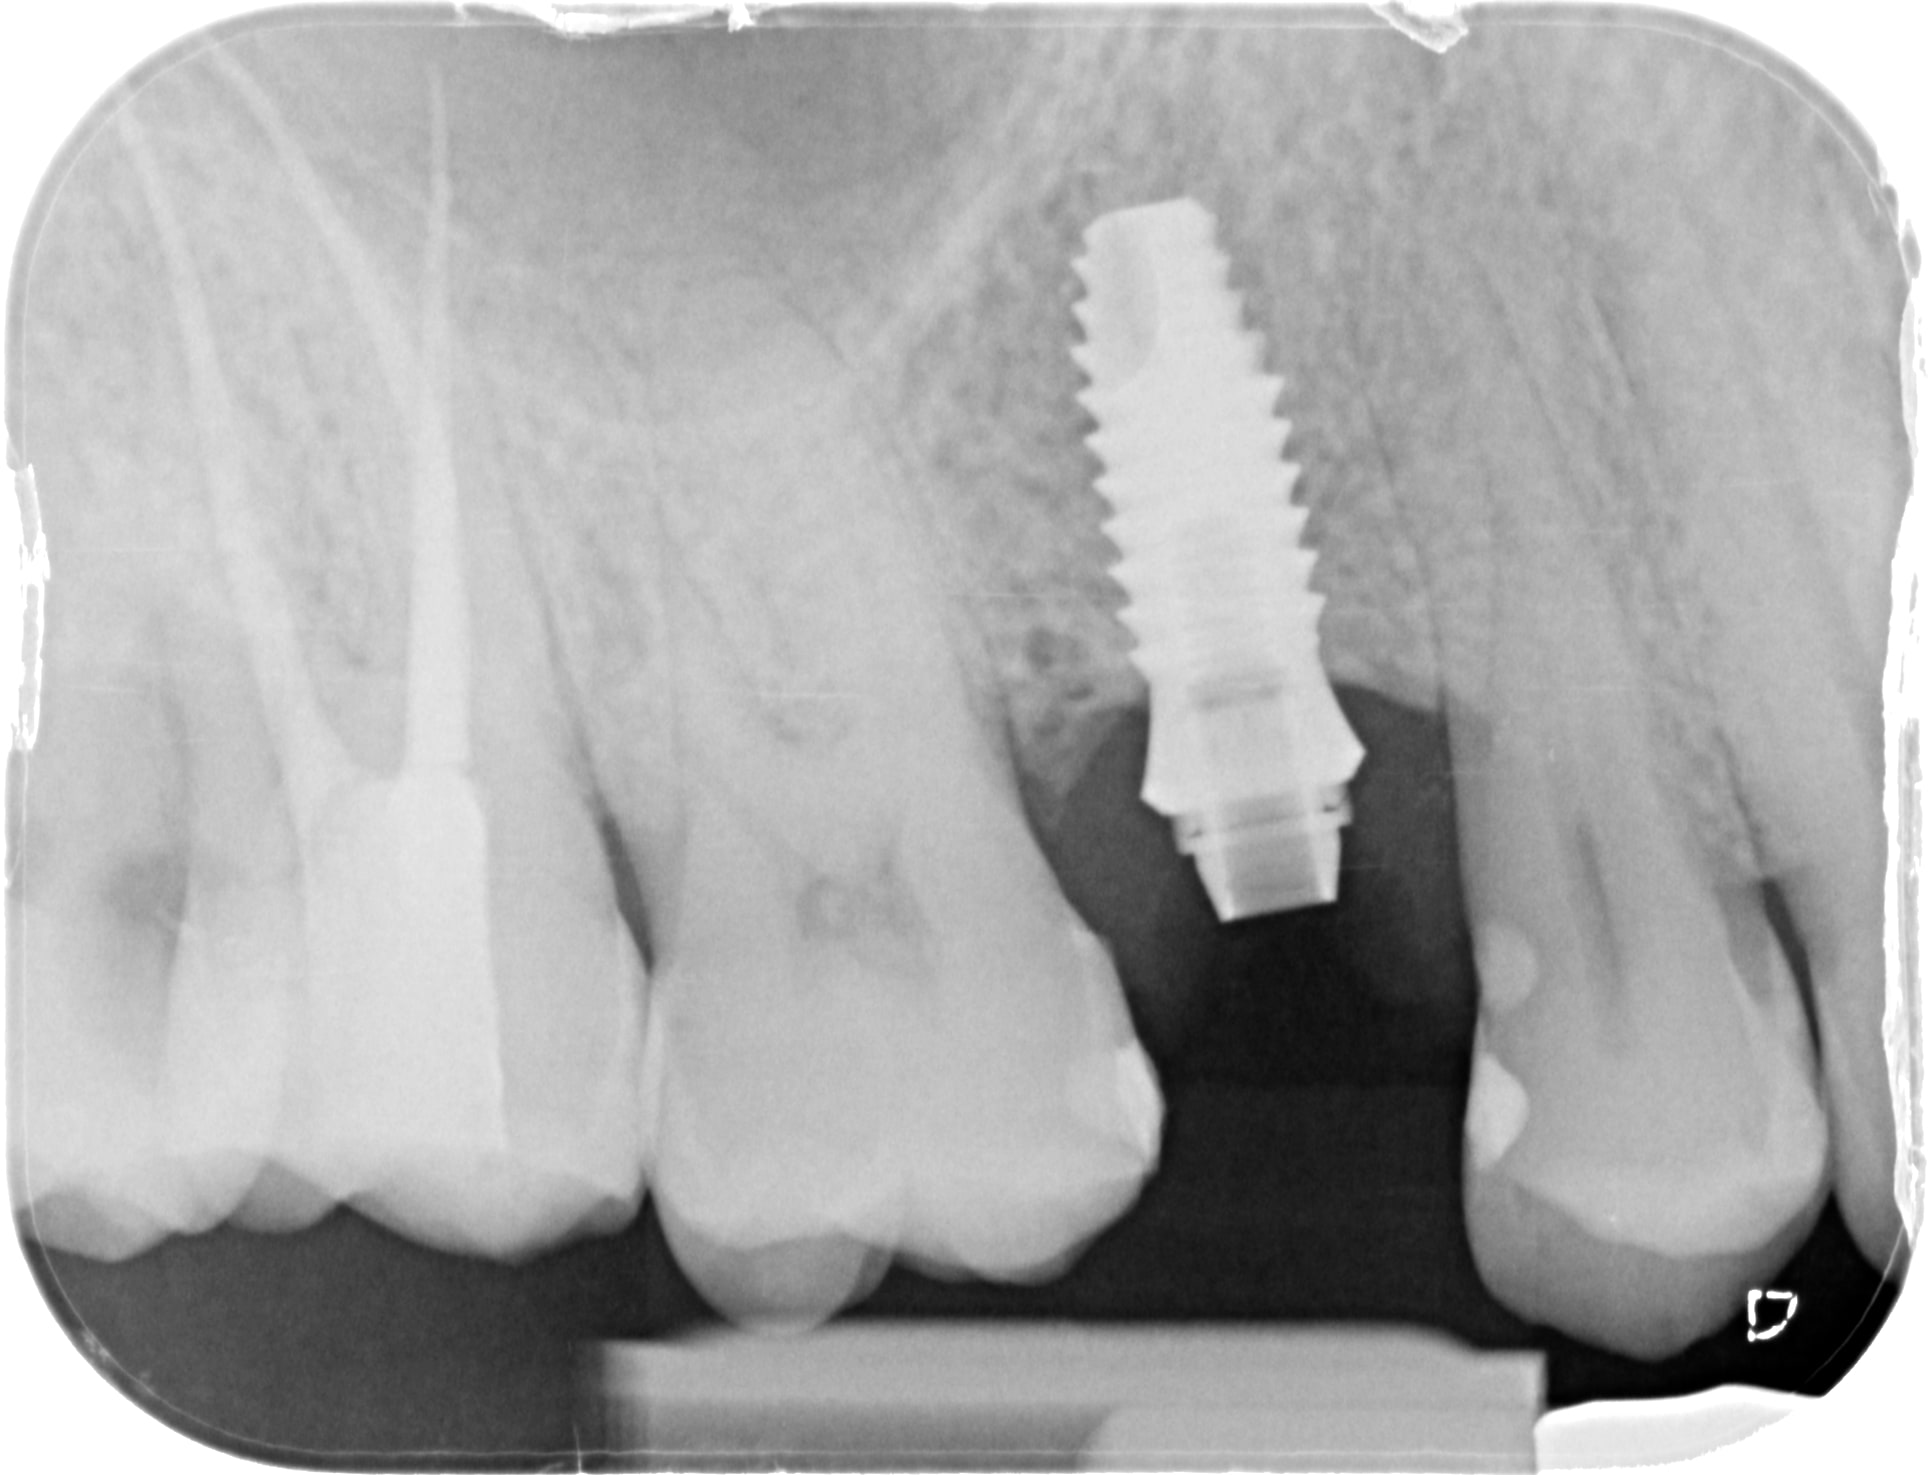

c'est un implant type Apolonia CSM qui est un implant avec octogone classique " Straumann"

L´implant (phibo TSA advance)est plutôt exotique conexion interne avec hexagone interne plus hexagone externe. Auquel il faut rajouter le pilier pro-unic qui transforme le basar en un cône. Il y a plusieur hauteurs de pilier ce qui implique plusieurs longueurs de vis fde fixatión.

c'est sûr qu'avec les références c'est plus facile....comme quoi l'identification à partir d'une radio c'est pas une science exacte....

3x25mm diametre 25 revo-s